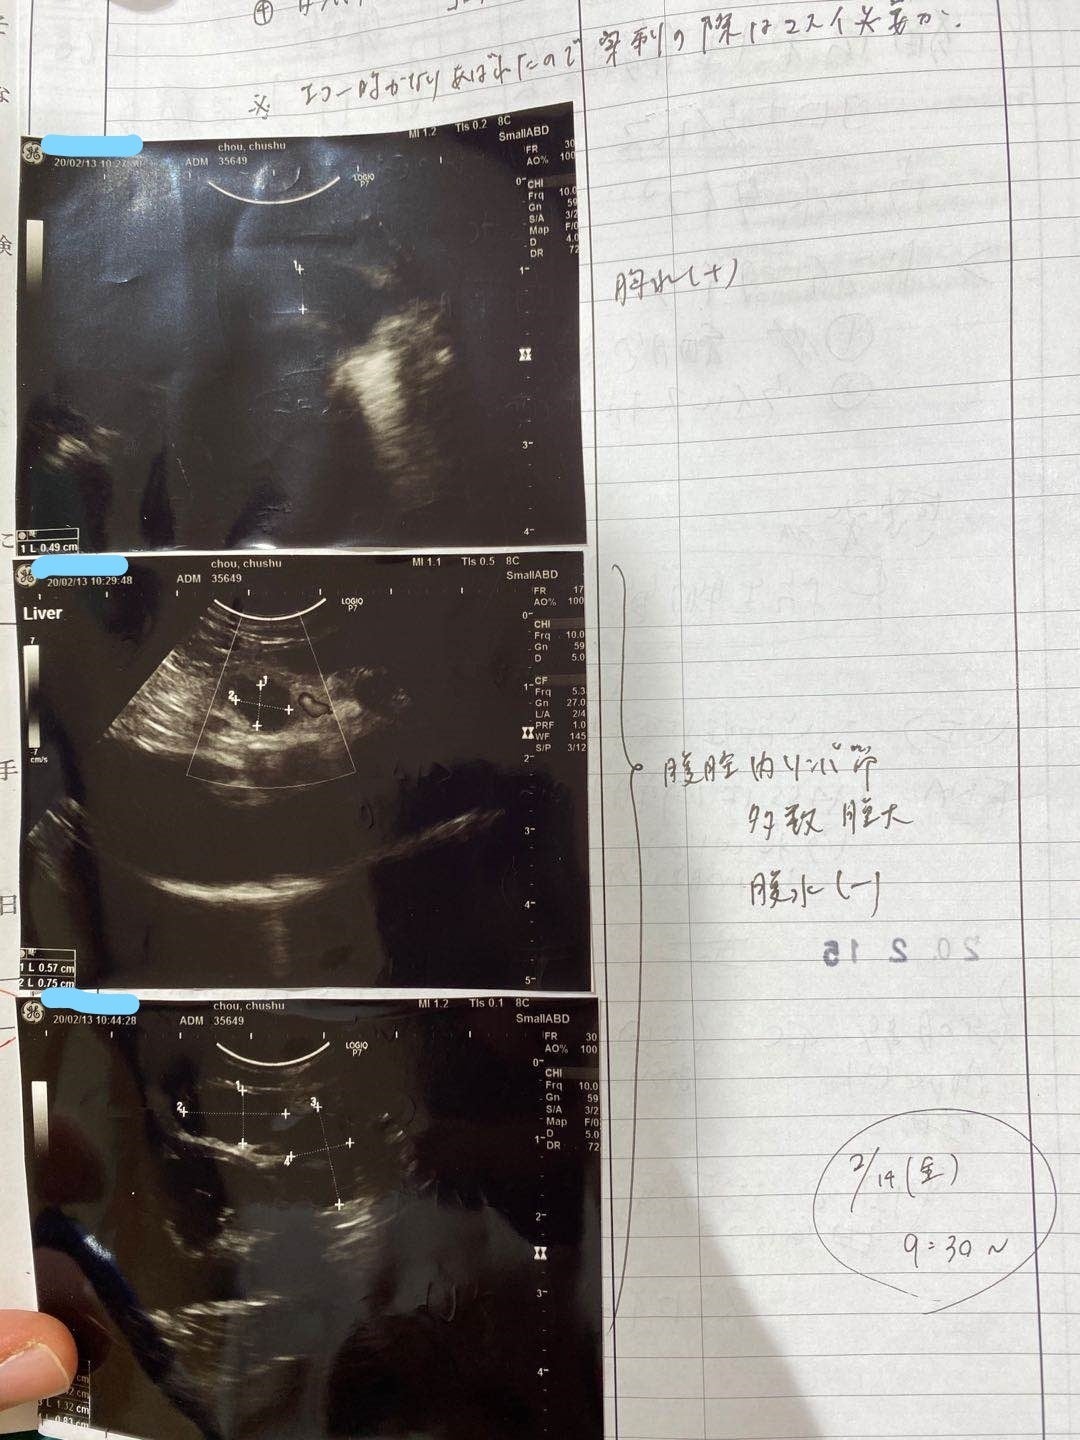

2/13去勢手術するため、身体検査をするとき、肺の中に薄い水影があって、念のため詳しい検査を行いました。

症状が軽い、判断が難しく、少し観察の時間が必要けど、最悪の場合はFIPを罹っているの可能性があると言われて、でも別の病気の可能性もあると言われました。3/9でレントゲン検査すると、水影が少し薄くになって、4月の検査も同じになって、FIPの可能性ではないかもと思います。けど、5月の検査はあまり変わらないになって、22日で急に発症になりました。前を振り返って見て、ずっと自分を責め続いている。

5/25家の近くの協力病院に行って、痛く辛い検査をして、中期混合型と診断されました。

腹水がたまっています

肉芽腫が見つかります

39℃の熱と重度の貧血もあります

強い炎症もあります